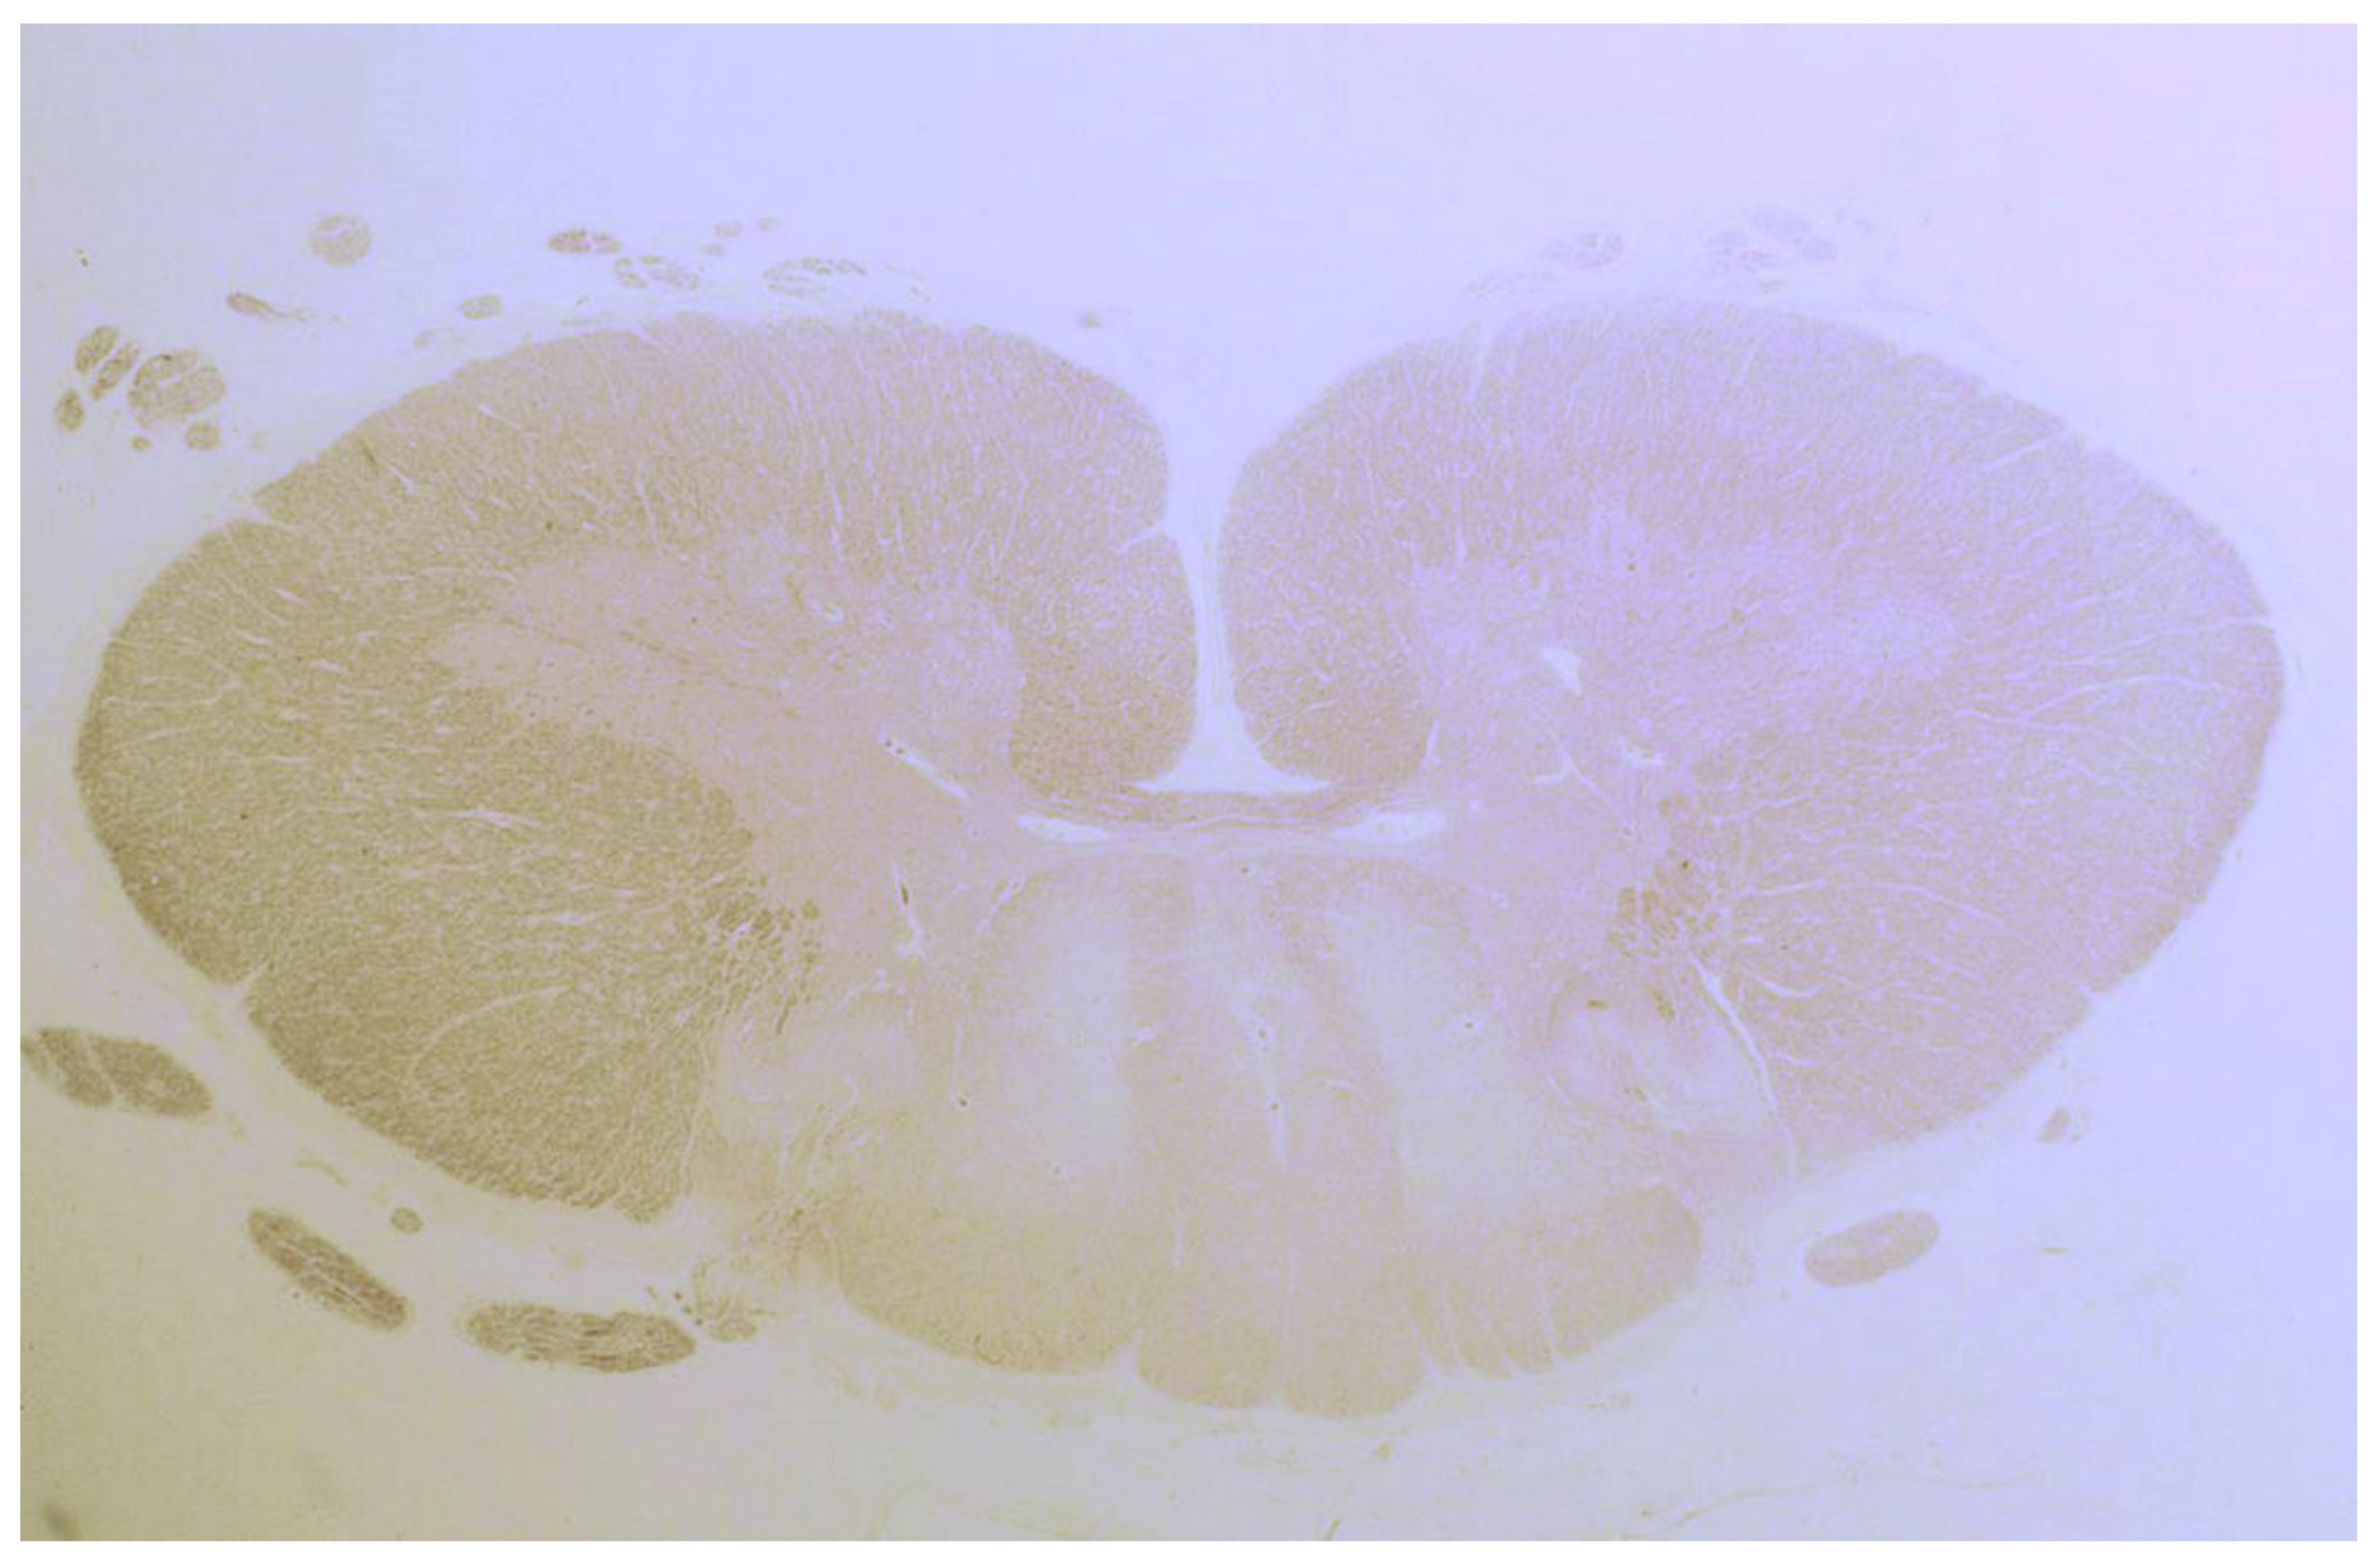

| Bhatia 1995, UK | 1 | Brain Spinal cord | Loss of Purkinje cells and cells in inferior olives; Cerebellar gliosis; Astrocytosis of the granular layer, dentate nucleus & inferior olives |

| Cooke 1966, UK (I) * | 9 | Brain Spinal cord | Loss of Purkinje cells; atrophy and gliosis of the dentate nucleus, cerebrum, inferior olives, thalamus and hypothalamus; demyelination of post. & ant.-lat. columns; focal perivascular lymphocytic cuffing, chromatolysis and sudanophil lipophages throughout the CNS. |

| Finelli 1980, USA | 1 | Brain Spinal cord | Loss of Purkinje and granular layer cells; Neuronal loss & gliosis basal ganglia, inferior olives, substantia nigra; Demyelination ant. & lat. corticospinal tracts |

| Hadjivassiliou 1998, UK | 2 | Brain Spinal cord | Loss of Purkinje cells; Cerebellar atrophy & astrocytic gliosis & vacuolation of neutrophils; Diffuse infiltration of lymphocytes & perivascular cuffing of T-lymphocytes in the cerebellum and the post. columns |

| Hadjivassiliou 2006, UK ** | 1 | Brain | Capillary changes in the white matter, hippocampus and olives marked by vascular and perivascular inflammatory cell infiltrates (CD68+ cells and a smaller CD45Ro+ cell population). Purkinje cell loss and Bergmann gliosis and loss of neurons in the inferior olives |

| Kinney 1982, USA | 1 | Brain | Loss of Purkinje cells; atrophy, gliosis of the dentate nucleus, cerebellar granular layer, thalamus, hypothalamus & periaqueductal grey; Senile plaques in the neocortex & hippocampi; Cerebral gliosis subcortical & white matter |

| Mittelbronn 2010, Germany | 1 | Brain | Loss of Purkinje cells & cerebellar granular layer cells; Cerebellar atrophy and astrocytic gliosis; Severe neuronal loss inferior olives & accumulation of corpora amylacea. Cerebral reactive astrogliosis and microglial activation Inflammation dominated by CD8+/granzyme B+ & CD20-/CD138- diffuse infiltrates & perivascular cuffing in the cerebellum and brainstem |

| Nanri 2011, Japan | 1 | Brain | Loss of Purkinje cells; Minimal cerebellar atrophy; Mild Bergmann gliosis. Empty basket cells, Edematous splitting of Purkinje cell layer, loss of granular cells. No lymphocytic infiltration (CD3-, CD4-, CD8-, CD20-, CD68-, CD79A-) |